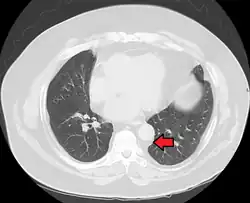

Mediastinal lipomatosis